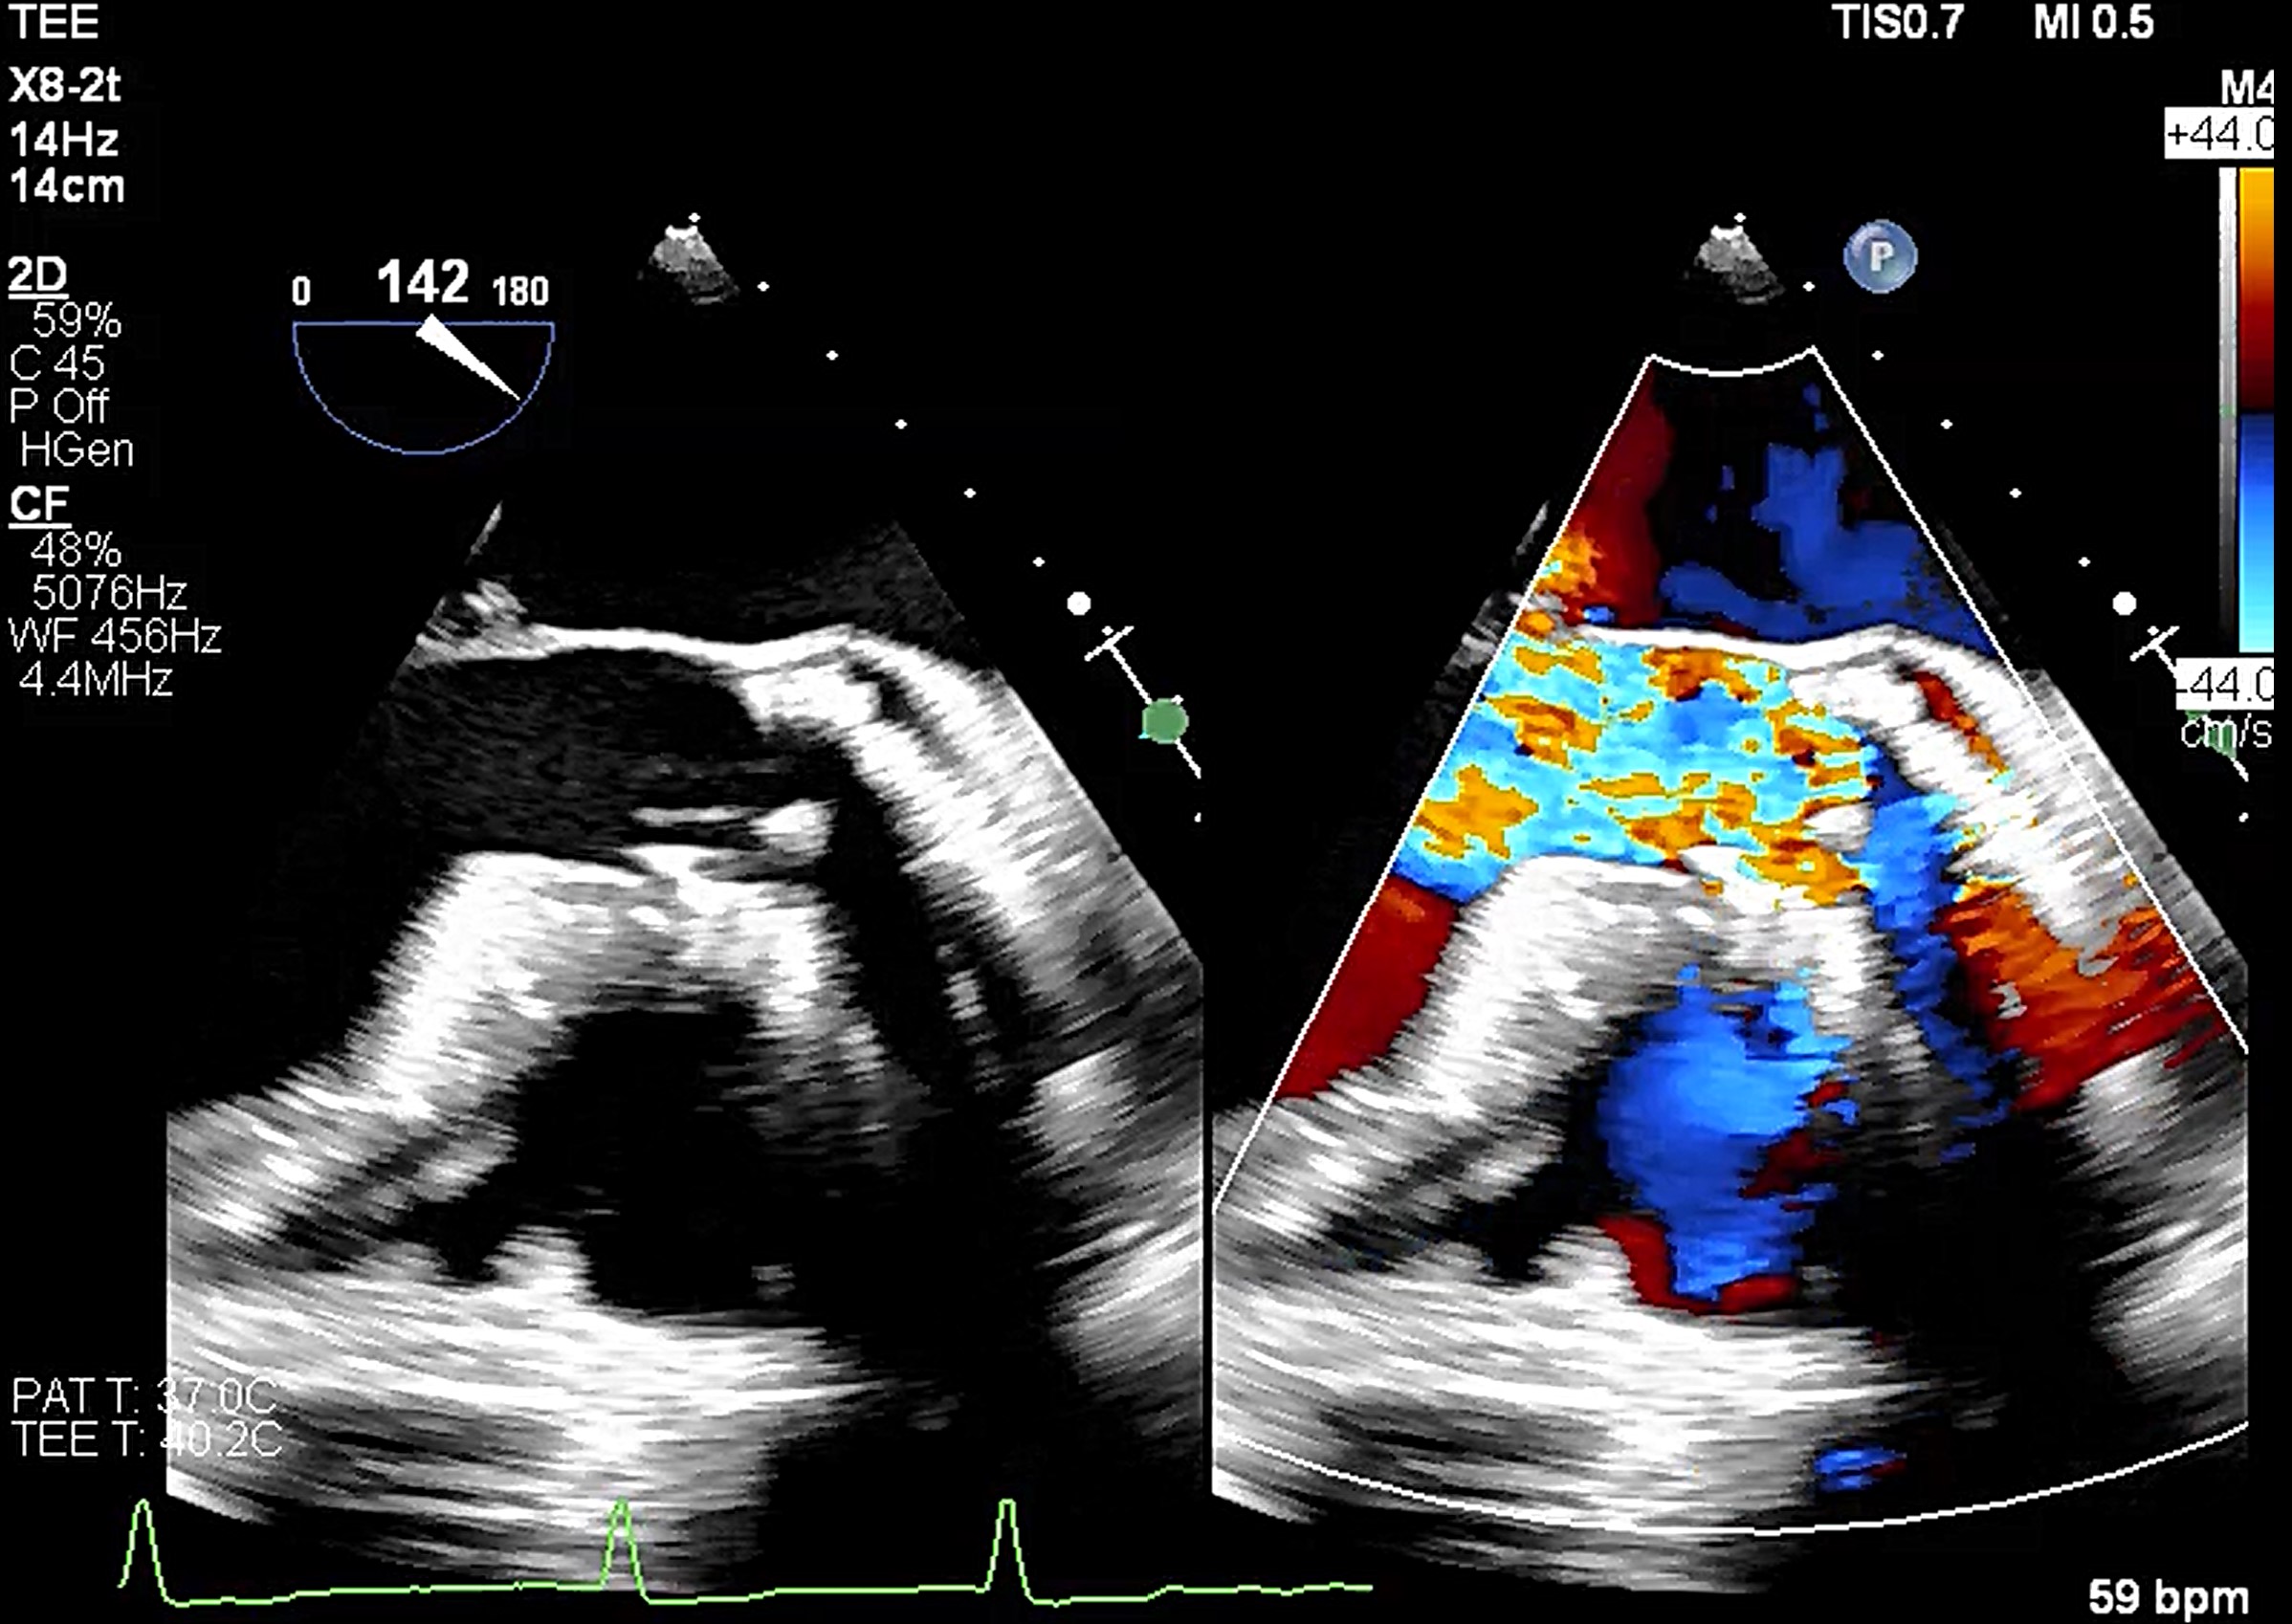

Transesophageal echocardiography revealed severe aortic regurgitation due to THV leaflet perforation following untreated infective endocarditis, along with a preexisting paravalvular leak caused by the calcified raphe of the type 1 bicuspid aortic valve.Given the patient’s deteriorating clinical status despite inotropic support, and after three negative blood cultures and five weeks of antibiotic treatment, the heart team decided to proceed with transcatheter treatment.

A combined procedure including transcatheter closure of paravalvular leak and redo-TAVR, was performed under general anesthesia with transesophageal echocardiographic guidance.1. Bilateral approach via left femoral artery(8Fr non-kinking sheath), right femoral artery(16Fr E-sheath).2. We used a Terumo guide wire accompanied with AL/5F diagnostic catheter to cross the defect of paravalvular leak.3. MP/7F guide catheter accompanied with 6 x 40mm Mustang balloon crossed the paravalvular leak defect by using balloon assisted tracking technique.4. Wire exchanged to Confida super-stiff wire.5. Amplatzer Vascular Plug II 9-12mm occluder was deployed successfully under TEE guidance. 6. TEE showed paravalvular leak downgrade to mild. There was no nearby structure damage, no new pericardial effusion, nor coronary obstruction.7. An Extra-small Safari super-stiff wire was placed in the left ventricle.8. A 23mm Sapien 3 valve was deployed successfully with 1cc overfill.9. The paravalvular leak and valvular AR both sealed successfully, with only minimal paravalvular leak remain.10. The transvalvular mean pressure gradient was 9mmHg, and the valve functioned well.